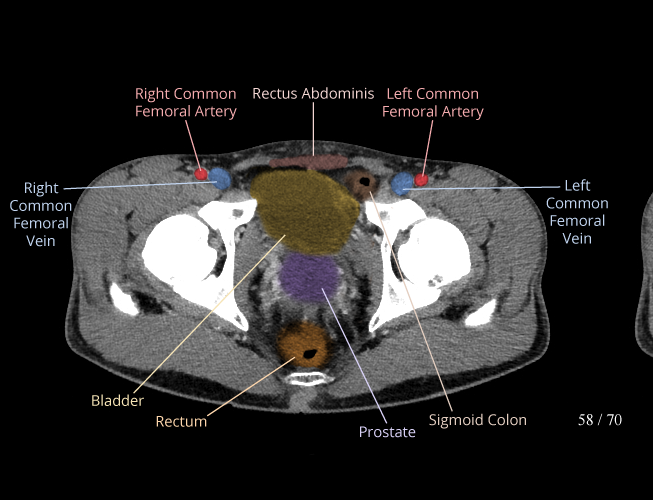

Pelvis

Covers pelvic MRI anatomy.